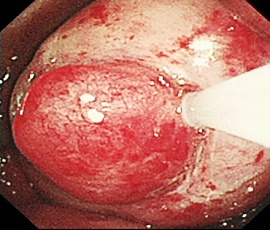

早期食道がん、胃がんを切らずに治す低侵襲な内視鏡治療

食道、胃における早期がんに対する内視鏡治療手技が発達し、根治ができる症例が増加

しており、従来の治療に代わる新しい治療法として注目されていますが、当院では可能

なかぎり食道、胃における早期がんに対しては内視鏡的粘膜下層剥離術(Endoscopic

submucosal dissection、以下ESD)を行っております。

ESD治療の実際

治療手技は内視鏡治療用の電気のメスで直接、病変部を切って剥ぎ取る方法です。高度

な内視鏡治療技術が要求されます。比較的大きな病変も一括切除が可能であるため局所

再発率を下げることや、顕微鏡による正確な病理診断を行い、がんの悪性度を正確に調

べることができることなどのメリットがあります。低侵襲治療と正確な病理診断を兼ね

た非常に優れた内視鏡的治療になりますが、しかし正確な病期診断が不可欠であり、早

期がんに対する各種画像検査を行い治療の適応を決定します。

全ての食道がん、胃がんの患者さんに対し、この治療法が可能というわけではありませ

ん。当院では根治度を保ちながら、できるだけ患者さんの負担を軽くするような手術を

心がけています。この治療法に関してご質問などありましたら外来でご相談ください。